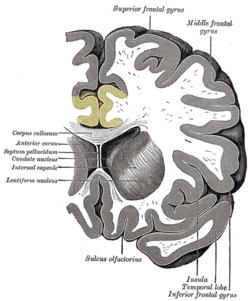

The cingulate cortex, a part of the limbic cortex, is a part of the brain situated in the medial aspect of the cerebral cortex. The cingulate cortex includes the entire cingulate gyrus, which lies immediately above the corpus callosum, and the continuation of this in the cingulate sulcus. The cingulate cortex is usually considered part of the limbic lobe.

Based on cerebral cytoarchitectonics it has been divided into the Brodmann areas 23, 24, 26, 29, 30, 31, 32 and 33. The areas 26, 29 and 30 are usually referred to as the retrosplenial areas.

Cingulum means "belt" in Latin. The name was likely chosen because this cortex, in great part, surrounds the corpus callosum. Cingulate is an adjective (cingularis or cingulatus). The cingulate cortex is a part of the "grand lobe limbique" of Broca (1898) that consisted (in addition to the olfactory part, which is no more considered there today) of a superior cingulate part, supracallosal; and an inferior hippocampic part, infracallosal. The limbic lobe was separated from the remainder of the cortex by Broca for two reasons: first because it is not convoluted, and second because the gyri are directed parasagittally (contrary to the transverse gyrification). Since the parasagittal gyrification is observed in non-primate species, the limbic lobe was thus declared to be "bestial". As with other parts of the cortex, there have been and continue to be discrepancies concerning boundaries and naming. Brodmann (1909), a student of Cécile Vogt-Mugnier and Oskar Vogt, who worked on Cercopithecus (and not much in human [Bailey and von Bonin]), elaborated a system of numeration that unfortunately had no typological logic (1, 2 and 3 are sensory, 4 is motor, 5 is parietal, 6 is premotor and 7 is again parietal!). Area 25 was even not placed by him in the same place in the human brain. Area 24 (anterior) was distinguished from 23 (posterior) on the basis that it was agranular. More recently, the typographical von Economo's system was adopted by Bailey and von Bonin. Simple typographical naming should be preferred, for evident heuristic purposes.